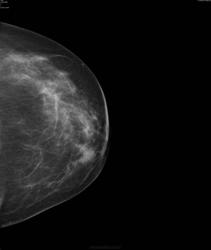

- https://radiomed.ru/sites/default/files/styles/case_slider_image/public/user/17752/bil7.jpg?itok=0k9-tdkT

Да, есть опухоль.. но пока небольшая

Слева опухолью Справа сгрукированые кальцинаты BIRADS 4 с двух сторон